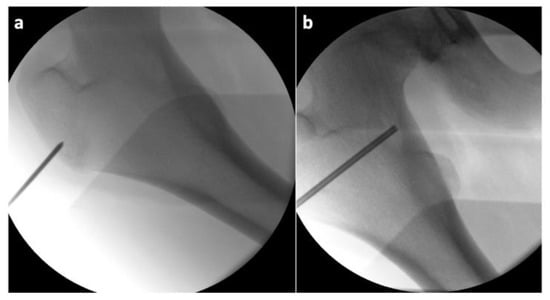

Figure 4.

Intraoperative X-ray of the proximal femur showing: (a) the insertion point of the Kirschner wire; (b) the position of the working cannula in the osteoma (the slightly brighter irregular oval area).

The correct positioning of the instruments was always controlled in two perpendicular projections (anteroposterior and lateral). Subsequently, we inserted an over-the-wire working cannula to draw a core biopsy sample for a further histologic examination (Figure 5).

Considering the findings and the persistent pain even after the regular administration of NSAIDs, a surgical solution was indicated in accordance with the patient and his legal representatives. Reaching the osteoma would be very challenging through a standard open approach, and the high level of invasiveness of such a procedure in a teenage patient would be unfavorable at the very least. Therefore, we turned to a more appropriate alternative in the form of a minimally invasive RFA. We implemented the OsteoCoolTM Bone Radio Frequency (RF) Ablation System (Sofamor Danek/Medtronic, Dublin, Ireland), which consists of an RF generator, a peristaltic pump, a connector hub with two channels for the RFA probes with an integrated cooling system for the active tips, and two channels for optional thermocouples []. The surgeon can intraoperatively choose the appropriate size of the active tip of the probe with different ablation volumes and times, depending on the size of the lesion. First, after a 2 cm skin incision above the greater trochanter, a Kirschner wire was inserted via a lateral pertrochanteric approach to the lateral hyperostotic margin of the osteoma. The insertion was carried out under direct radiographic control, using conventional C arm guidance (Figure 4).